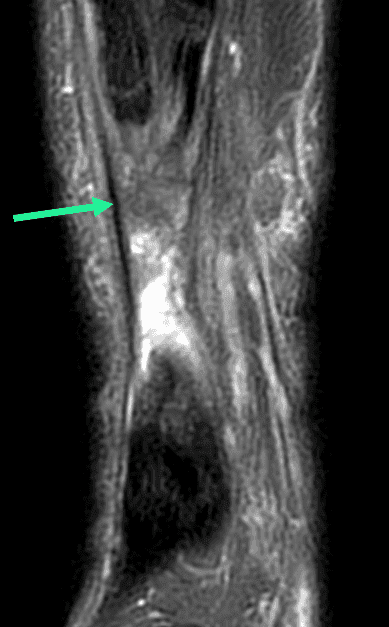

Large solution de continuité tendineuse en lien avec une rupture proximale complète du tenon calcanéen.

Dans ce cas précis, il existe un tendon plantaire grêle (flèches vertes) qui apparaît continu, épargné par la rupture tedineuse, ce cas de figure est parfois interprété à tort comme une rupture partielle du tendon calcanéen.

Il est important de rechercher la présence d'un tendon plantaire grêle sur le versant médial du tendon calcanéen, car ce tendon accessoire et inconstant peut être prélevé et utilisé dans la reconstruction chirurgicale du tendon calcanéen.

Coronal T2 FS